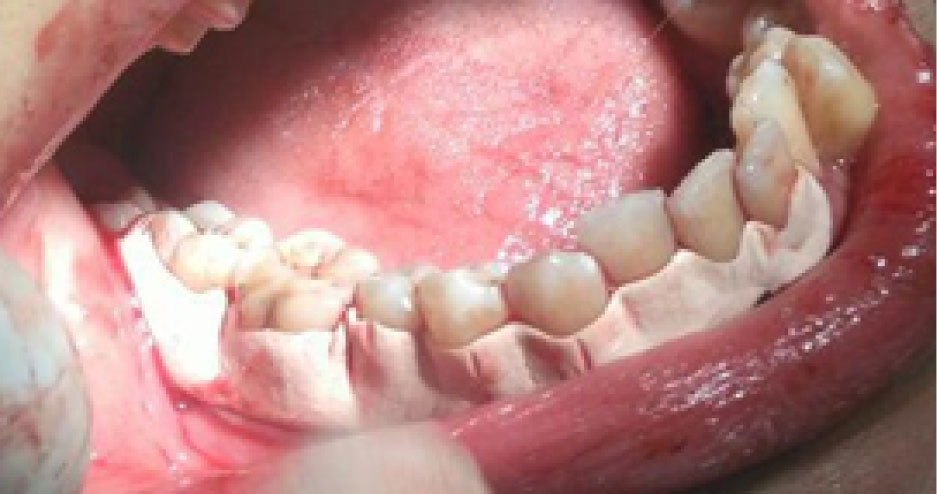

Flap surgery was performed in each quadrant following the standard protocol of site preparation, incision, flap reflection, and thorough debridement. Minimal bone contouring was performed in some cases of both groups, while no case required any bone grafting. Primary closure was achieved using 3-0 silk suture on a 3/8 circle reverse cutting needle. Thereafter, in the control group, Coe-PakTM was placed at the surgical sites (). Equal lengths of base and catalyst paste of this dressing were mixed on a glass slab according to manufacturers’ instructions. It was applied and pushed well into the embrasure spaces using moist gloved hands to mold it to the required contour. It was extended from one tooth mesial to the first suture to one tooth distal to the last suture of the surgical segment, extending from the cervical third of teeth to the mucogingival junction. Diplen LX dressing was placed in the intervention group (). Occlusal clearance over the dressing was also checked. The extent of the dressing was the same as described above with Coe-PakTM. In both cases, patients were given postoperative instructions and advised to rinse with 10 mL of 0.2% chlorhexidine gluconate solution twice daily for one week to control plaque. They were also prescribed ibuprofen tablets (600 mg three times daily for three days). On the 7th day after surgery, the periodontal dressing was removed in two parts (buccal and lingual) using a dental tweezer and a blunt probe. The patients were asked to fill an assessment questionnaire and rate the preferred dressing based on pain and discomfort experienced, taste, appearance, retention, burning sensation, and sensitivity experienced with each type of dressings. Wound healing index (WHI) parameter12was also evaluated at the surgical site on the 7th and 14th days after surgery in both groups.Patient-reported parametersincluded pain assessment based on the verbal rating scale and patient’s preference based on burning sensation, hypersensitivity, appearance, taste, and retention of dressings. This parameter was also evaluated on the 3rd and 7th days after surgery in both groups. Evaluation of wound healing was based on the parameters of tissue color, bleeding in response to palpation, the presence of granulation tissue, and the condition of incision margin. Each of these four parameters was separately assessed on the scale of 1 (very poor) to 5 (excellent), and the total score was finally divided by 4 to achieve the WHI score.

joddd-16-135-g001

Figure 1. COE PAK Dressing used in control group.